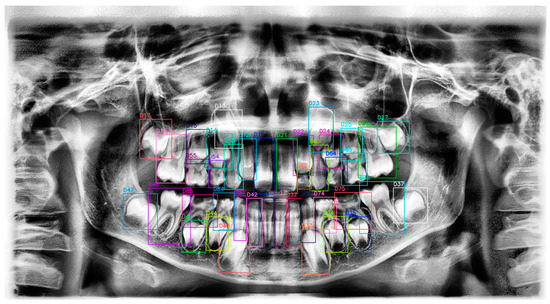

Evaluation of the Performance of a YOLOv10-Based Deep Learning Model for Tooth Detection and Numbering on Panoramic Radiographs of Patients in the Mixed Dentition Period

2.4. Ground Truth Labeling